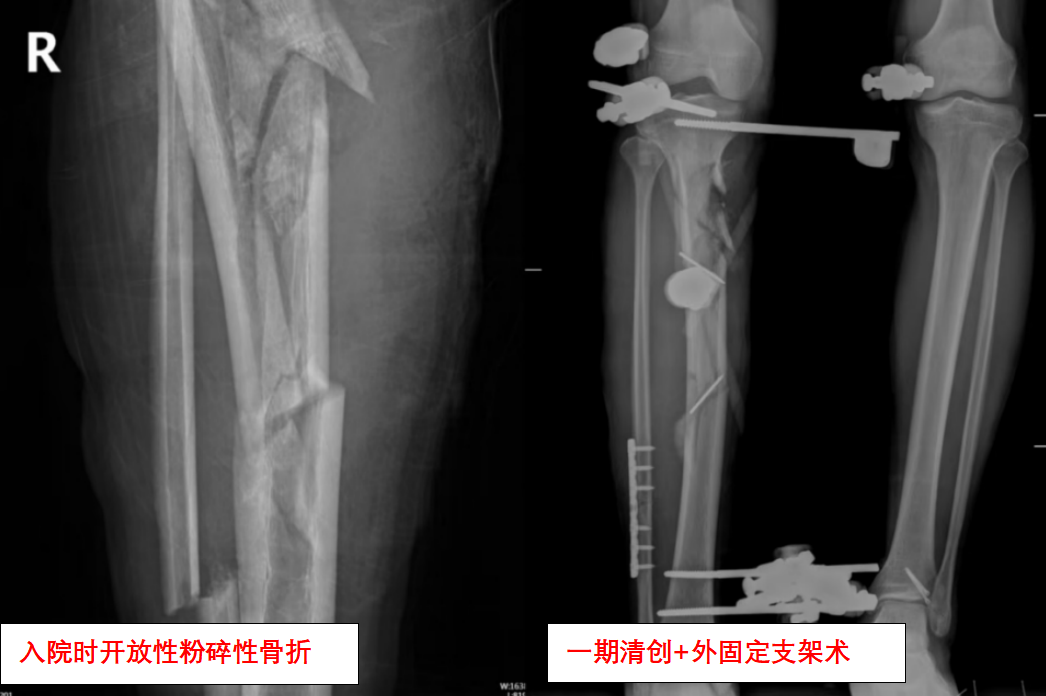

事发当晚,黎先生被紧急送往医院,创伤中心立即启动绿色通道。检查显示:右胫腓骨粉碎性骨折伴大面积皮肤撕脱,血管神经损伤,污染严重。主刀医生、创伤骨科副主任柯迪峰回忆,像黎先生这类损伤若处理不及时,极易感染导致截肢甚至危及生命。

医护团队连夜实施急诊手术:清创、外支架固定、骨牵引、VSD负压引流……4小时的奋战稳住了黎先生的生命体征,也为后续治疗争取了时间。

“第一次手术不是终点,而是马拉松的开始。”创伤骨科副主任缪旭东说道。缪旭东介绍,黎先生的保肢之路远比想象艰难。由于创伤严重,黎先生先后经历了外支架固定术:重建骨骼稳定性;多次清创+植皮术:对抗感染并修复软组织;骨移植术:填补缺损的骨组织;功能重建术:恢复关节活动能力。